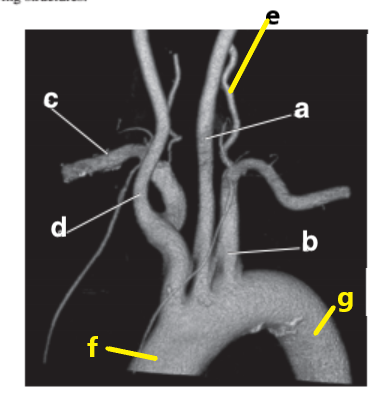

Which letter is the left subclavian artery ?

b

Which letter is the Right common carotid artery ?

d

What is letter a ?

Brachiocephalic trunk

Which letter is the Right coronary artery ?

c

Which letter is the Right vertebral artery ?

f

Which letter is the right subclavian artery ?

g

Which letter is the Left common carotid ?

a

Which letter is the brachiocephalic trunk ?